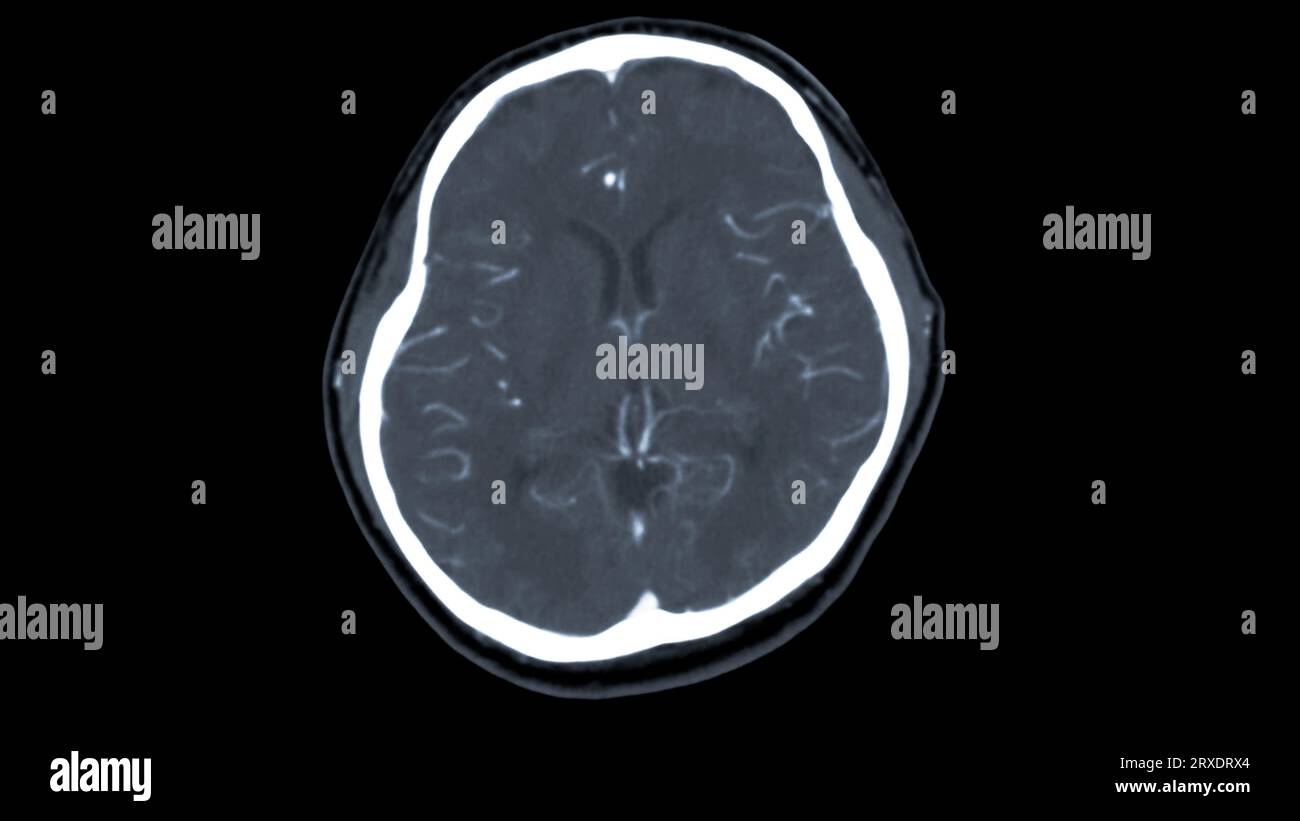

Scanner du cerveau avec le produit de contraste d'injection pour le diagnostic de tumeur cérébrale, les maladies d'AVC et les maladies vasculaires. Banque D'Imageshttps://www.alamyimages.fr/image-license-details/?v=1https://www.alamyimages.fr/scanner-du-cerveau-avec-le-produit-de-contraste-d-injection-pour-le-diagnostic-de-tumeur-cerebrale-les-maladies-d-avc-et-les-maladies-vasculaires-image567016971.html

Scanner du cerveau avec le produit de contraste d'injection pour le diagnostic de tumeur cérébrale, les maladies d'AVC et les maladies vasculaires. Banque D'Imageshttps://www.alamyimages.fr/image-license-details/?v=1https://www.alamyimages.fr/scanner-du-cerveau-avec-le-produit-de-contraste-d-injection-pour-le-diagnostic-de-tumeur-cerebrale-les-maladies-d-avc-et-les-maladies-vasculaires-image567016971.htmlRF2RXDRX3–Scanner du cerveau avec le produit de contraste d'injection pour le diagnostic de tumeur cérébrale, les maladies d'AVC et les maladies vasculaires.

Scanner du cerveau avec le produit de contraste d'injection pour le diagnostic de tumeur cérébrale, les maladies d'AVC et les maladies vasculaires. Banque D'Imageshttps://www.alamyimages.fr/image-license-details/?v=1https://www.alamyimages.fr/scanner-du-cerveau-avec-le-produit-de-contraste-d-injection-pour-le-diagnostic-de-tumeur-cerebrale-les-maladies-d-avc-et-les-maladies-vasculaires-image567016972.html

Scanner du cerveau avec le produit de contraste d'injection pour le diagnostic de tumeur cérébrale, les maladies d'AVC et les maladies vasculaires. Banque D'Imageshttps://www.alamyimages.fr/image-license-details/?v=1https://www.alamyimages.fr/scanner-du-cerveau-avec-le-produit-de-contraste-d-injection-pour-le-diagnostic-de-tumeur-cerebrale-les-maladies-d-avc-et-les-maladies-vasculaires-image567016972.htmlRF2RXDRX4–Scanner du cerveau avec le produit de contraste d'injection pour le diagnostic de tumeur cérébrale, les maladies d'AVC et les maladies vasculaires.

Scanner du cerveau avec le produit de contraste d'injection pour le diagnostic de tumeur cérébrale, les maladies d'AVC et les maladies vasculaires. Banque D'Imageshttps://www.alamyimages.fr/image-license-details/?v=1https://www.alamyimages.fr/scanner-du-cerveau-avec-le-produit-de-contraste-d-injection-pour-le-diagnostic-de-tumeur-cerebrale-les-maladies-d-avc-et-les-maladies-vasculaires-image567016966.html

Scanner du cerveau avec le produit de contraste d'injection pour le diagnostic de tumeur cérébrale, les maladies d'AVC et les maladies vasculaires. Banque D'Imageshttps://www.alamyimages.fr/image-license-details/?v=1https://www.alamyimages.fr/scanner-du-cerveau-avec-le-produit-de-contraste-d-injection-pour-le-diagnostic-de-tumeur-cerebrale-les-maladies-d-avc-et-les-maladies-vasculaires-image567016966.htmlRF2RXDRWX–Scanner du cerveau avec le produit de contraste d'injection pour le diagnostic de tumeur cérébrale, les maladies d'AVC et les maladies vasculaires.